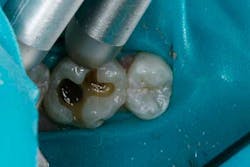

An example of an ideal case for which bulk filled composite (i.e., Tetric EvoCeram® Bulk Fill) is indicated is a 43-year-old female who presented with a defective amalgam restoration on the occlusal of tooth No. 14 (Figs. 1 and 2). The treatment plan involved removing the defective amalgam restoration, any secondary caries, and restoring the tooth with a direct bulk-fill composite (i.e., Tetric EvoCeram® Bulk Fill).

The tooth was prepared and a total etch technique utilizing 37% phosphoric acid was performed (Figs. 3 through 5). After the etchant was rinsed, a desensitizer was placed and blotted to leave a moist dentin surface for bonding (Fig. 6). The bonding agent was applied; the ethanol solvent was air evaporated using a warm air dryer; and the adhesive light-cured for 10 seconds (Figs. 7 and 8).